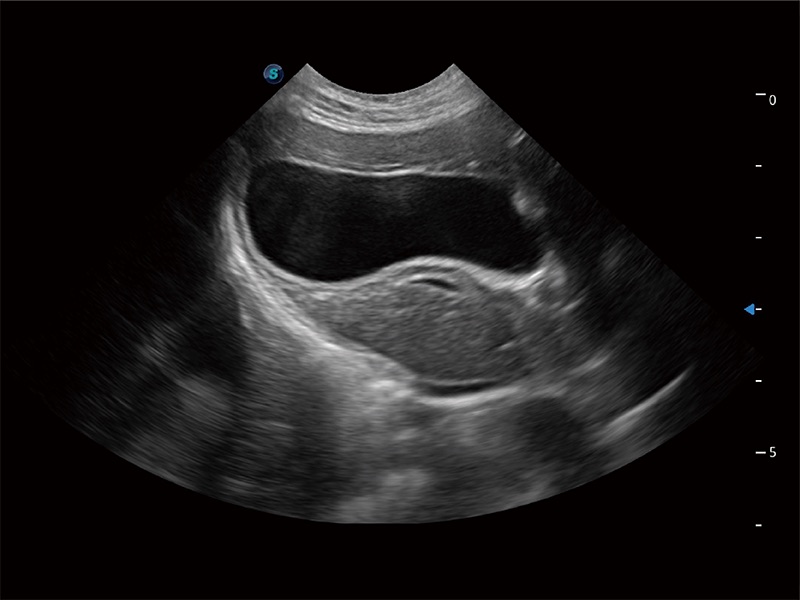

(猫)胆囊

(犬)胎儿四腔心

(猫)二尖瓣M型